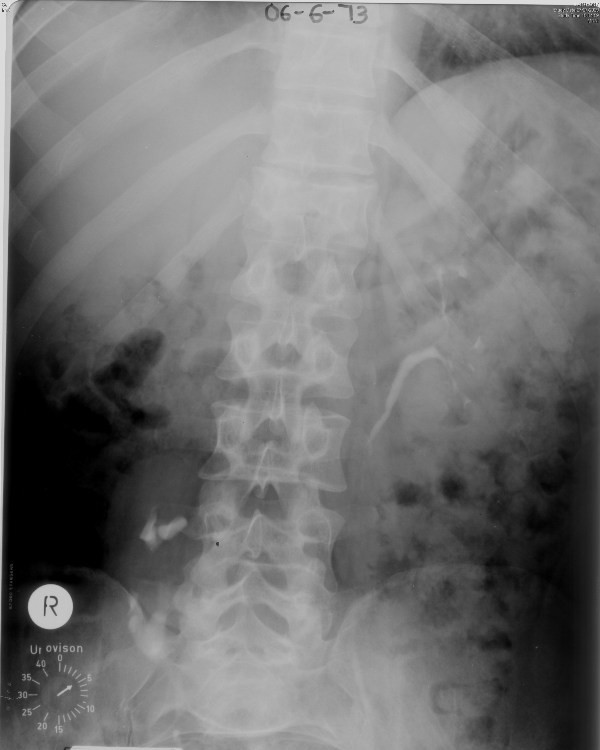

Figure 1From: Lessons we learn from review of urological procedures performed during three decades in a spinal cord injury patient: a case reportIntravenous urography (06 June 1973): Five minutes film shows normal left kidney with undilated pelvicalyceal system and ureter. Right kidney is located at L4-5 level and malrotated.Back to article page